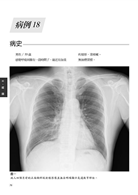

病例18 甲狀腺乳突癌合併氣管侵犯 76

(Tracheal tumor-thyroid papillary carcinoma with trachea invasion)